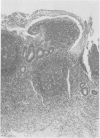

Faecal stream diversion may induce inflammatory changes in the defunctioned segment of the large intestine. These changes are predominantly mucosal, although confusing histological features including granulomas may be present. The pathology of 15 defunctioned rectal stumps has been studied. All patients had previously undergone urgent total colectomy for ulcerative colitis and rectal stumps had been left in situ while they awaited pelvic ileal reservoir construction. All rectal stumps showed predominantly mucosal disease but there were additional features such as florid lymphoid follicular hyperplasia (12 cases), transmural inflammation (nine cases), granulomas (four cases), fissures (eight cases), and changes akin to ischaemia or to pseudomembraneous colitis (four cases). These changes may result from a combination of defunctioning and of active ulcerative proctitis. Some induce a histological appearance that may mimic Crohn's disease. Nevertheless review of all 15 colectomy specimens showed unequivocal ulcerative colitis and none of the patients has subsequently shown any clinical, radiological, or pathological evidence to support a diagnosis of Crohn's disease. Histology of the rectal stump in ulcerative colitis may lead to an erroneous diagnosis of Crohn's disease and the patient may subsequently be denied the advantage of a pelvic ileal reservoir.